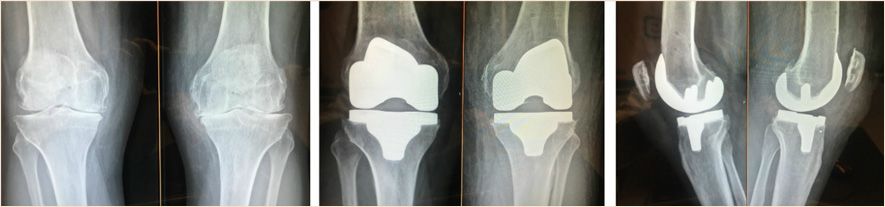

More recently, Winnock de Grave introduced the inverse kinematic alignment (iKA) as new patient specific alignment concept [39] Winnock de Grave, P., Luyckx, T., Claeys, K. et al. Higher satisfaction after total knee arthroplasty using restricted inverse kinematic alignment compared to adjusted mechanical alignment. Knee Surg Sports Traumatol Arthrosc 30, 488–499 (2022). https://doi.org/10.1007/s00167-020-06165-4. iKA favors the restoration of tibial joint line obliquity as first step (Figure 1). This is followed by resection of the posterior and distal femur bone by using the gap balancing technique to achieve ligament balance without releasing soft tissues. By resecting equal amounts of bone on the medial and lateral tibial condyle the native tibial joint line obliquity is restored (Figures 2, 3, 4). In iKA also boundaries are set to attenuate extreme morphotypes. When the target zones of iKA, rKA and MA are compared, the iKA target zones matches a higher proportion of native knee alignment, followed by rKA and MA [40] Winnock de Grave, P., Luyckx, T., Van Criekinge, T. et al. Inverse kinematic alignment accommodates native coronal knee alignment better in comparison to adjusted mechanical alignment and restricted kinematic alignment. Knee Surg Sports Traumatol Arthrosc (2023). https://doi.org/10.1007/s00167-023-07326-x. Analysis of the tibial position in iKA in the coronal plane shows a mean postoperative MPTA of 86,5°, corresponding to the native joint line obliquity [40] Winnock de Grave, P., Luyckx, T., Van Criekinge, T. et al. Inverse kinematic alignment accommodates native coronal knee alignment better in comparison to adjusted mechanical alignment and restricted kinematic alignment. Knee Surg Sports Traumatol Arthrosc (2023). https://doi.org/10.1007/s00167-023-07326-x. The femoral position with the iKA shows a mean external rotation of 2° relative to the posterior condylar axis (PCA) and 2° varus position according to the native LDFA of 86° [8], Chao TW, Geraghty L, Dimitriou P, Talbot S. Averaging rotational landmarks during total knee arthroplasty reduces component malro- tation caused by femoral asymmetry. J Orthop Surg Res 2017;12:74, http://dx.doi.org/10.1186/s13018-017-0575-2 [PMID: 28499396; PMCID: PMC5429545]. [29], Ng CK, Chen JY, Yeh JZY, Ho JPY, Merican AM, Yeo SJ. Distal femoral rotation correlates with proximal tibial joint line obliquity: a considera- tion for kinematic total knee arthroplasty. J Arthroplasty 2018;33:1936–44, http://dx.doi.org/10.1016/j.arth.2017.12.025 [Epub 2017 Dec 28. PMID: 29395720]. [39] Winnock de Grave, P., Luyckx, T., Claeys, K. et al. Higher satisfaction after total knee arthroplasty using restricted inverse kinematic alignment compared to adjusted mechanical alignment. Knee Surg Sports Traumatol Arthrosc 30, 488–499 (2022). https://doi.org/10.1007/s00167-020-06165-4. Whereby, when using off the shelf implants, this varus orientation of the trochlear groove leads to an optimal patellofemoral tracking [36] V Vigdorchik JM, Wakelin EA, Koenig JA, Ponder CE, Plaskos C, DeClaire JH,Lawrence JM, Keggi JM, Impact of Component Alignment and Soft Tissue Release on 2 Year Outcomes in TKA, J Arthroplasty (2022), https://doi.org/10.1016/j.arth.2022.04.042.. A clinical study comparing iKA with MA at 12 months follow up shows that higher proportions of iKA knees are satisfied and higher proportion of iKA knees that reach the patient accepted symptom state (PASS) thresholds for the Oxford Knee Score (OKS) [39] Winnock de Grave, P., Luyckx, T., Claeys, K. et al. Higher satisfaction after total knee arthroplasty using restricted inverse kinematic alignment compared to adjusted mechanical alignment. Knee Surg Sports Traumatol Arthrosc 30, 488–499 (2022). https://doi.org/10.1007/s00167-020-06165-4.

1. In the coronal plane

With iKA, the aim is to restore the native joint line obliquity (JLO), by restoring the individual MPTA and to restore the native limb alignment (HKA axis). The native MPTA is restored by performing equal bony resections medial and lateral on the tibial plateau. The MPTA is restored within the boundaries of 84° (varus) and 92° (valgus) preventing extreme implant positions. These boundaries represent native tibial alignment in 93% of Caucasian knees. [40] Winnock de Grave, P., Luyckx, T., Van Criekinge, T. et al. Inverse kinematic alignment accommodates native coronal knee alignment better in comparison to adjusted mechanical alignment and restricted kinematic alignment. Knee Surg Sports Traumatol Arthrosc (2023). https://doi.org/10.1007/s00167-023-07326-x The postoperative coronal limb alignment (HKA) is restored within the boundaries of 6° varus and 3° valgus. Postoperative limb alignment up to 6° varus have shown no deleterious effect on implant survival in long term survival studies. [1], Abdel M, Ollivier M, Parratte S, Trousdale R, Berry D, Pagnano M. Effect of post-operative mechanical axis alignment on survival and functional outcomes of modern[19], Hungerford DS, Krackow KA.Total joint arthroplasty of the knee. Clin Orthop Relat Res. 1985; 192: 23-33https://doi.org/10.1097/00003086-198501000-00004[35] Vendittoli PA, Martinov S, Blakeney WG. Restricted kinematic alignment, the fundamentals, and clinical applications. Front Surg. 2021; 8: 697020. https://doi.org/10.3389/fsurg.2021.697020 On the femoral side, the femoral component is positioned using the gap balancing technique to gain a symmetric extension gap. Furthermore the femoral implant restores the native medial joint line height as good as possible which will result in MCL isometry and prevent mid-flexion instability [24] MacDessi SJ, Griffiths-Jones W, Harris IA, Bellemans J, Chen DB. The arithmetic HKA (aHKA) predicts the constitutional alignment of the arthritic knee compared to the normal contralateral knee, a matched-pairs. Bone Joint Open 2020;1-7:339–345. doi: 10.1302/2633-1462.17..